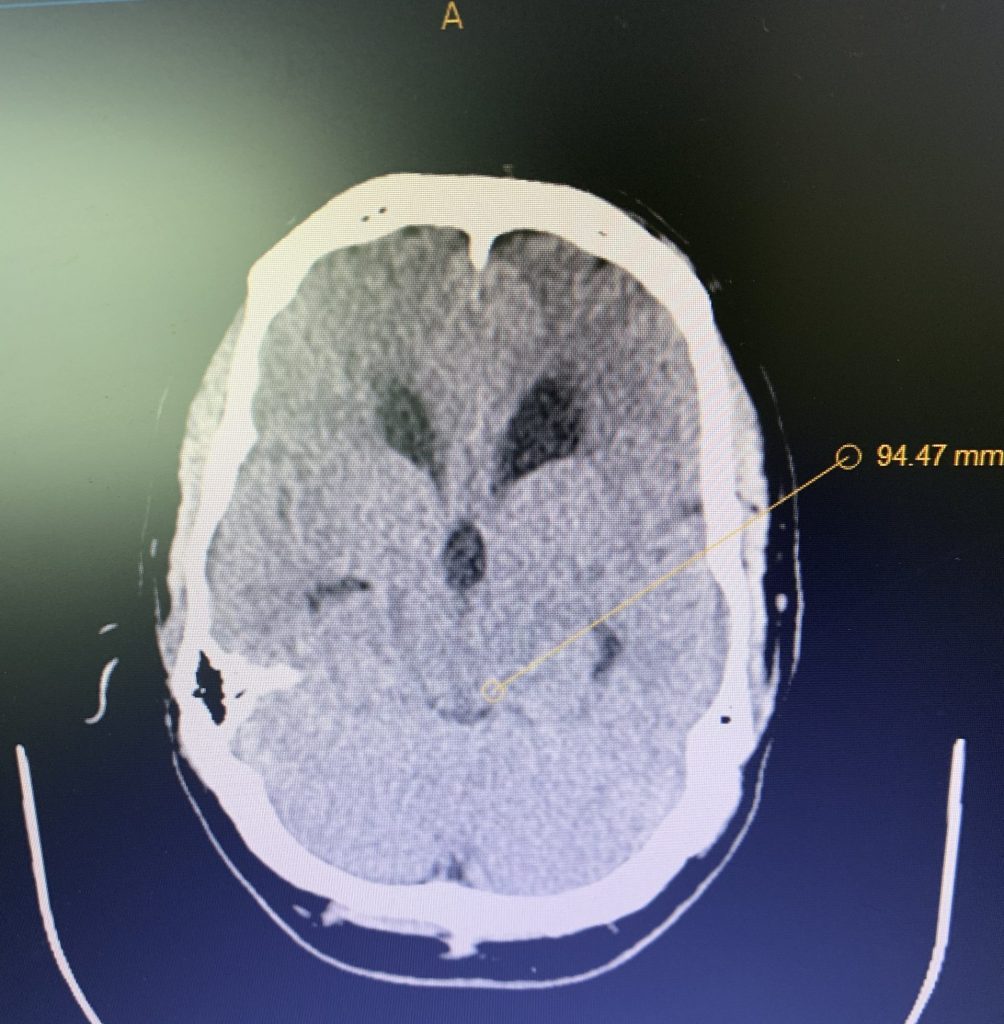

Neurosurgeons Collaborate to Treat Giant Symptomatic Meningioma

Author: Ramin Rak M.D., F.A.A.N.S., F.C.N.S., Jonathan L. Brisman M.D., F.A.C.S., Read More!